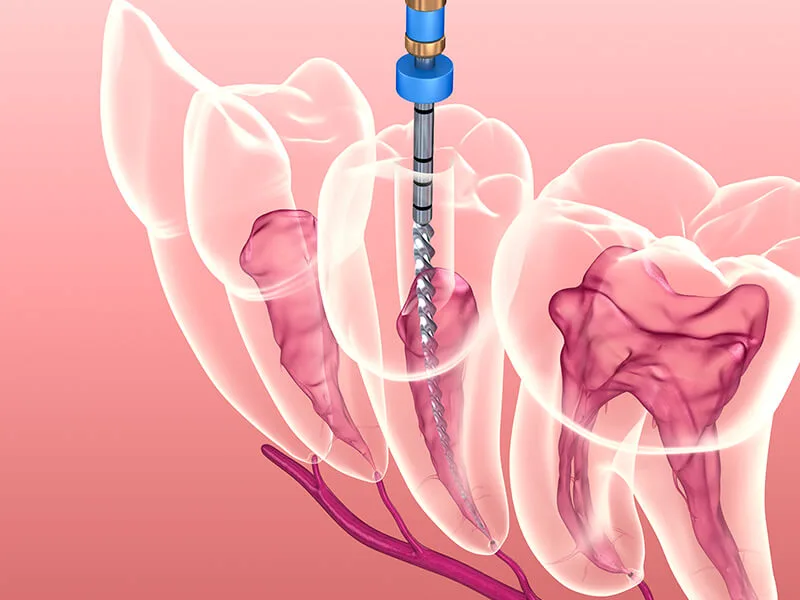

Uma unidade focada nessa especialidade oferece procedimentos de qualidade superior. Isso ocorre devido à prática constante do profissional em lidar com anatomias complexas e casos que exigem rigor técnico:

Limpeza profunda e desinfecção minuciosa dos canais radiculares;

Vedação interna realizada com materiais biocompatíveis de excelência;

Aplicação de métodos que visam a eliminação total de focos infecciosos.

O atendimento em uma unidade preparada é muito mais individualizado. O cirurgião avalia cada caso de forma exclusiva, resultando em um plano de ação adaptado às particularidades biológicas de cada arcada atendida.

Além disso, o uso de recursos atuais promove maior segurança nos processos. Equipamentos modernos auxiliam na realização de diagnósticos ágeis, fundamentando intervenções que respeitam a integridade dos tecidos bucais do paciente.

O especialista sabe como conduzir o tratamento de canal de maneira suave, desmistificando o receio comum a esse tipo de sessão. O foco é salvar a estrutura original do dente, protegendo a harmonia e a mastigação.